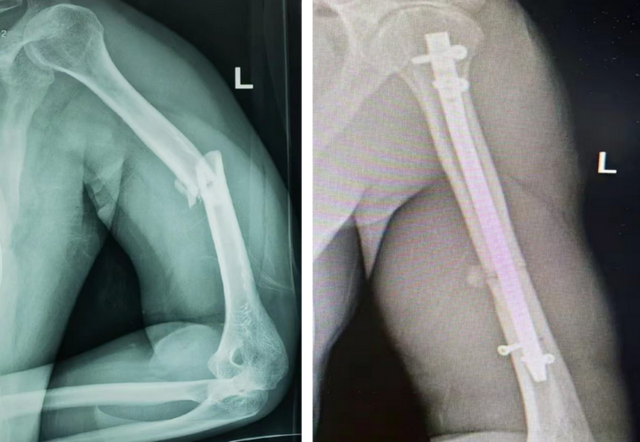

肱骨骨折髓内钉内固定